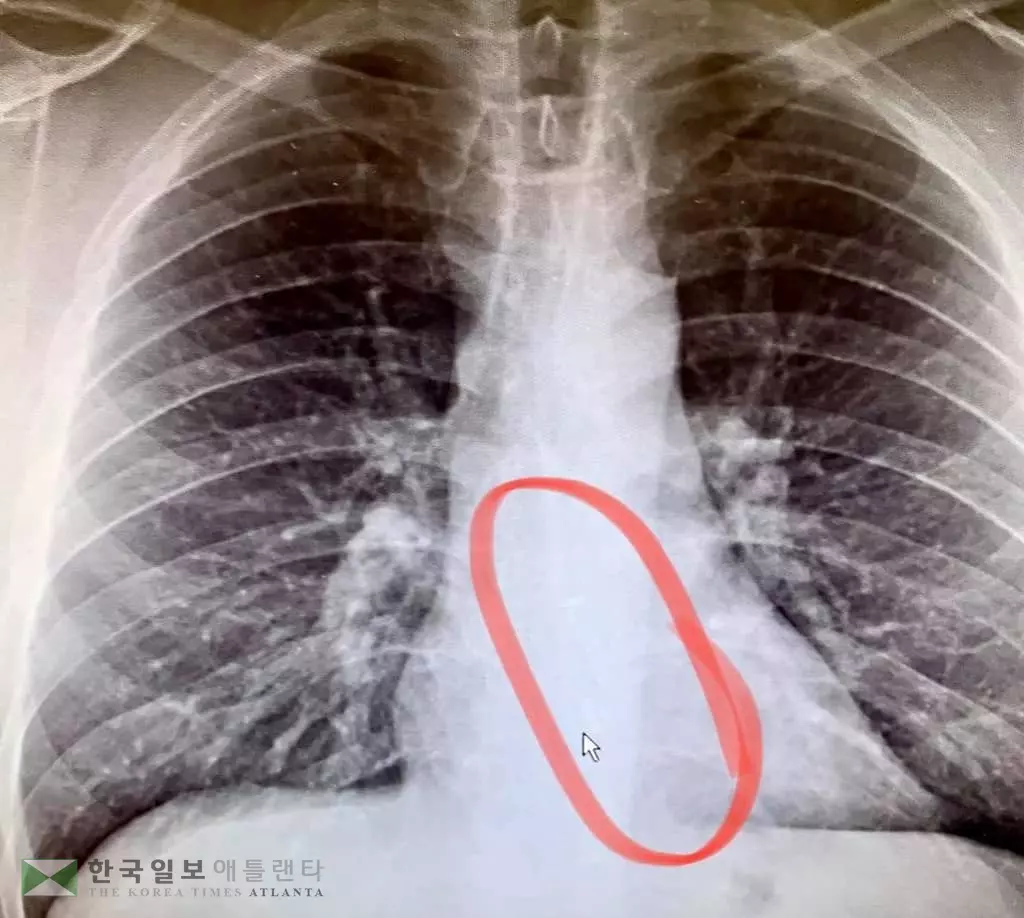

엑스레이 사진 촬영 결과 고티에의 식도 하단에 무선 이어폰이 걸려 있었다. 그는 응급 내시경 시술로 약 2인치 길이의 이어폰을 빼낼 수 있었다.